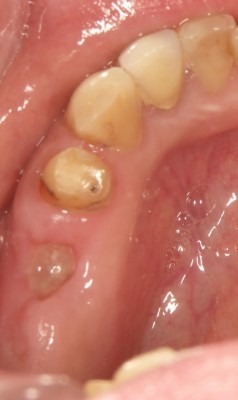

インプラントの術前・術後 Nさん